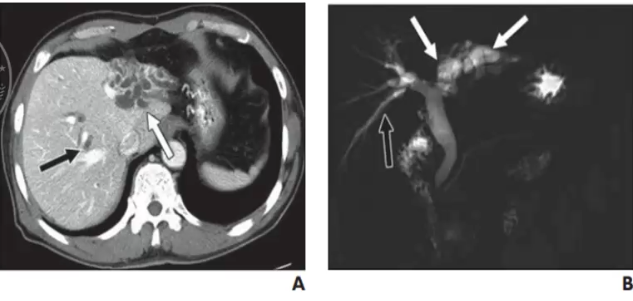

❖ IPNB典型表现为扩张胆管腔内边界清晰的乳头状肿块或绒毛状软组织影

❖ 增强实性部分动脉期明显强化,门脉期及延迟期呈等或稍低密度

❖ MRCP肝内胆管局部囊状扩张,内见结节状充盈缺损上下游胆管明显扩张

❖ I型:导管内肿块伴近端胆管扩张

❖ II型:不成比例胆管扩张不伴可见肿块

❖ Ⅲ型:导管内肿块伴近远端胆管扩张

❖ IV型:局灶囊性扩张伴乳头状肿块